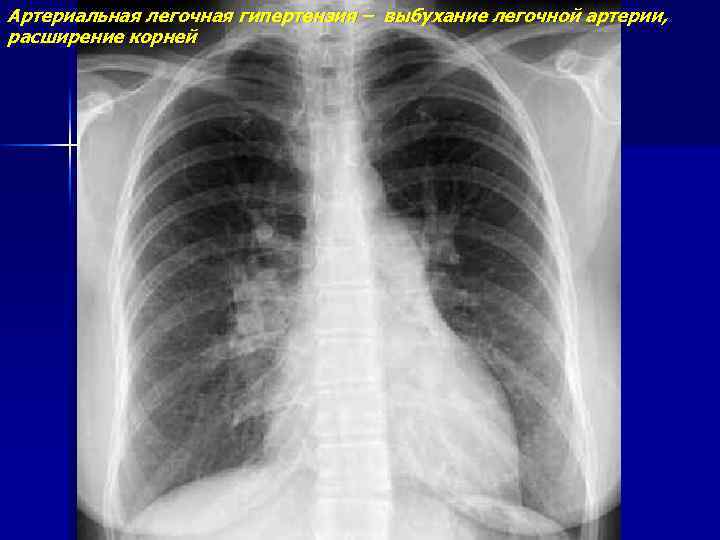

Артериальная легочная гипертензия – выбухание легочной артерии, расширение корней